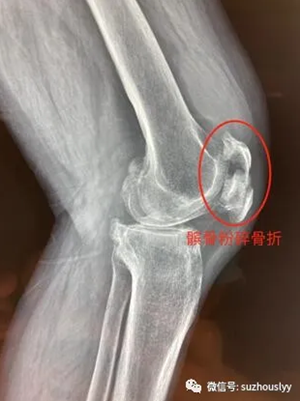

患者高某,67岁,膝关节反复疼痛、行走不便多年,重度骨性关节炎表现,长期保守治疗,效果欠佳。由于膝关节疼痛行走不便,患者不慎摔倒,拍片显示髌骨粉碎骨折,随即收住我院骨一关节科接受住院治疗。

伤后片子显示髌骨粉碎骨折